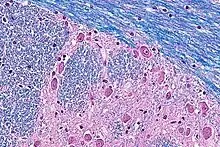

Under the stain, myelin fibers appear blue, neuropil appears pink, and nerve cells appear purple. Tissues sections are treated over an extended period of time (usually overnight) and then differentiated with a lithium carbonate solution.[4]